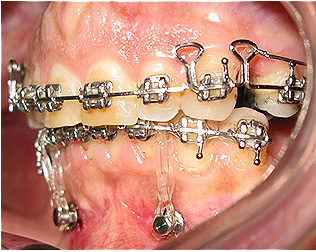

Após dois anos de tratamento ortodôntico.

![]() |